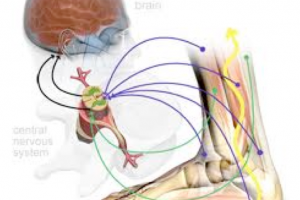

また膝の曲げ伸ばしの際には必ず軸運動が発生します。

この軸運動があることにより、曲げ伸ばしがきちんとできると言い換えることもできます。